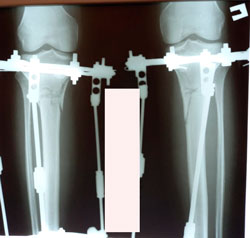

на фиксации

image-22-01-21-05-20-7.jpg

image-22-01-21-05-20-3.jpg